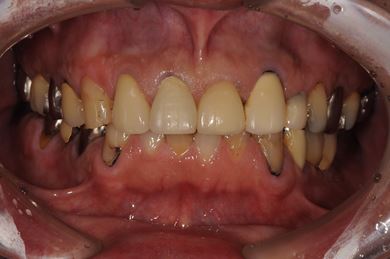

治療前

• 治療前